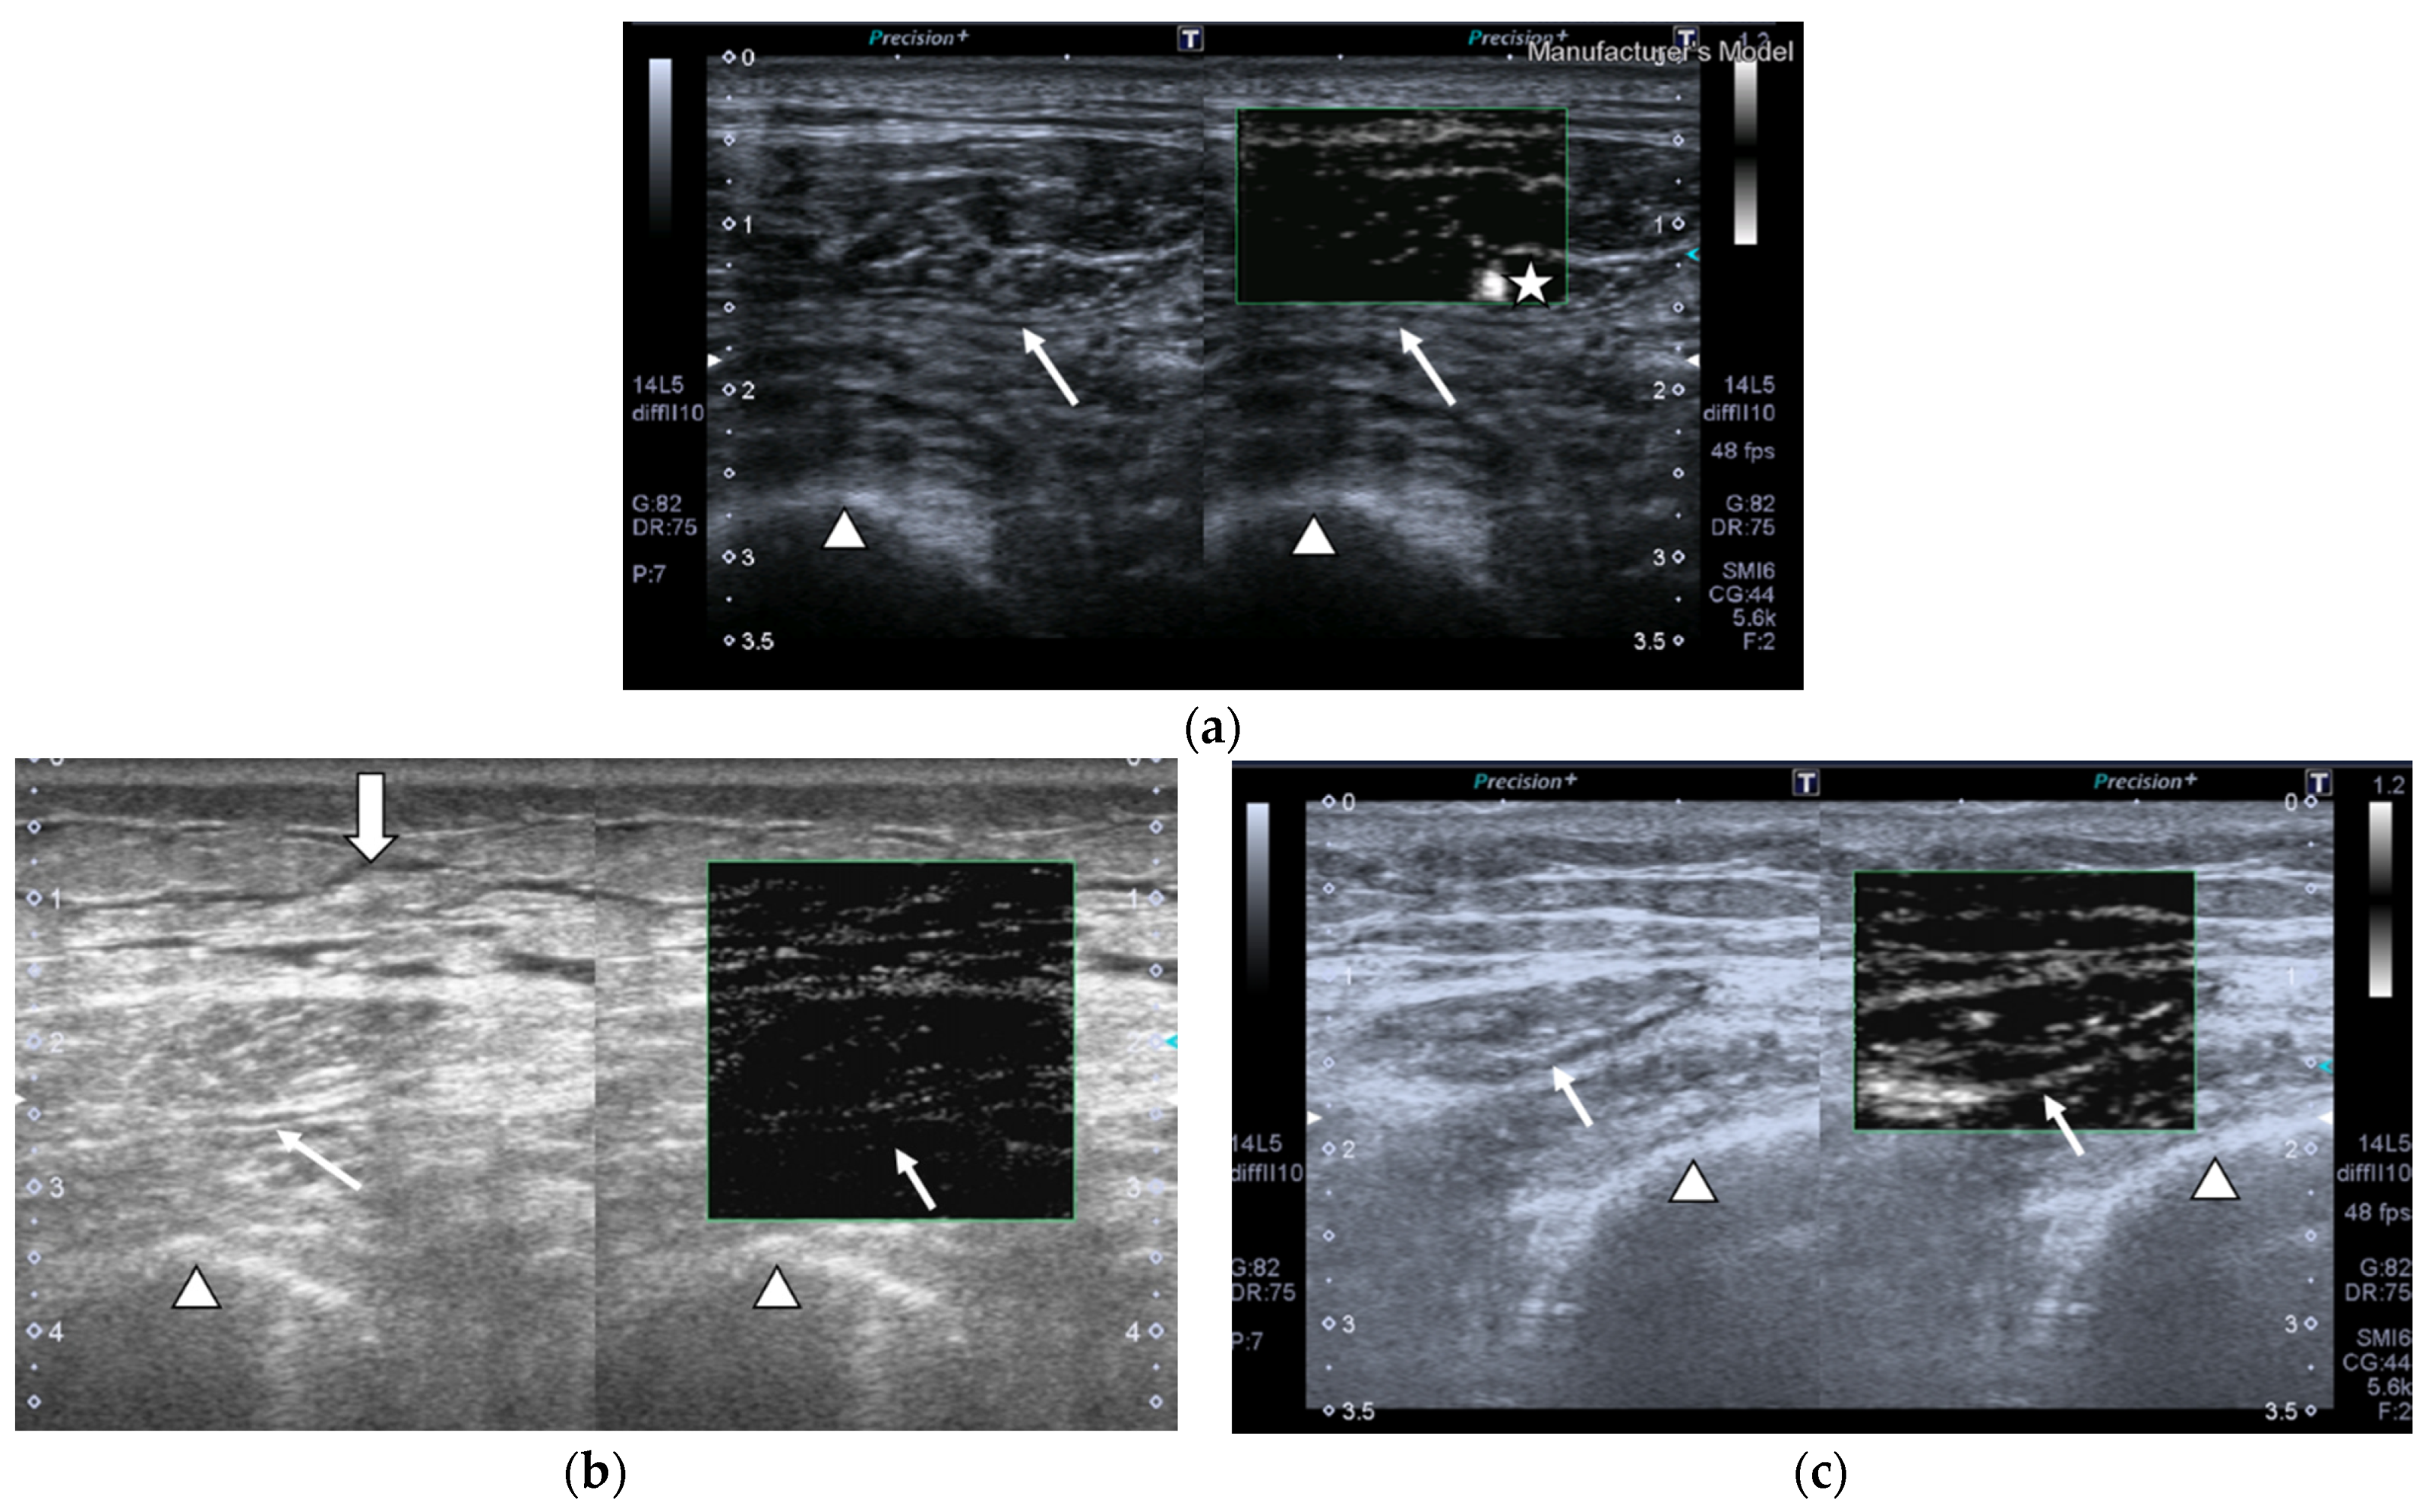

SMI images of a patient and a healthy control are displayed in Figure 2.

Figure 2.

Transversal QRF muscle US scan and the superb microvascular imaging (SMI) built-in software that indicates microvascularization. (a)Transversal QRF muscle (arrow) US scan, femur (arrowhead). SMI image shows dot-like vessels and a penetrating vessel (star) for a matched healthy control (60 years old). (b) Transversal QRF muscle (arrow) US scan, femur (arrowhead); subcutaneous edema with intramuscular and interfacial fluid (thick arrow). SMI image shows dot-like vessels for a patient with multiorgan failure (58 years old). (c) Transversal QRF muscle (arrow) US scan, femur (arrowhead). SMI image shows minimal linear vessels for another patient with multiorgan failure (51 years old).